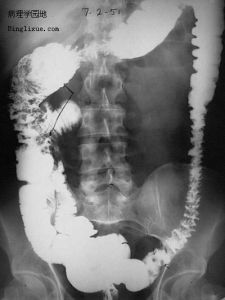

GARDNER綜合症2、X線檢查:凡懷疑有骨瘤或骨質異常增生者應攝正側位片,以了解有無皮質增厚或骨質增生。胃腸鋇餐造影和鋇劑灌腸雙重對比造影,均有助於發現消化道內的可疑息肉。